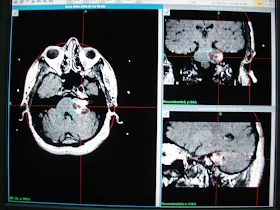

This, 26 years nice man from Karachi had undergone insertion of VP shunt on right side on November 22, 2010 on radio diagnosis of heterogeneous enhancing solid cum cystic mass in posterior fossa in fourth ventricle causing hydrocephalus. This was diagnosed when patient had presented with severe headache on and off associated with vomiting worst since last month and blurred vision since one month.

On referral, he had presented some improvement in headache and vomiting and significant improvement in blurring of vision. Clinical examination had revealed no obvious neurologic deficit. MRI brain spectroscopy had revealed markedly elevated Choline levels up to 399. Patient has referred us for the management with GKSRS. Risk of GKSRS explained all in Urdu along with requirement of strict follow up. These agreed upon wished to proceed. He had treatment with following prescription,

Target | Location | Prescription | Volume |

A | Ependymoma. | 12Gy @ 50% | 18.6 cm³ |

Multiple isocenters with 18, 14 & 8 mm collimator used in APS mode. He had discharged on tapering doses of Dexamethasone and advised follow up after 3 months